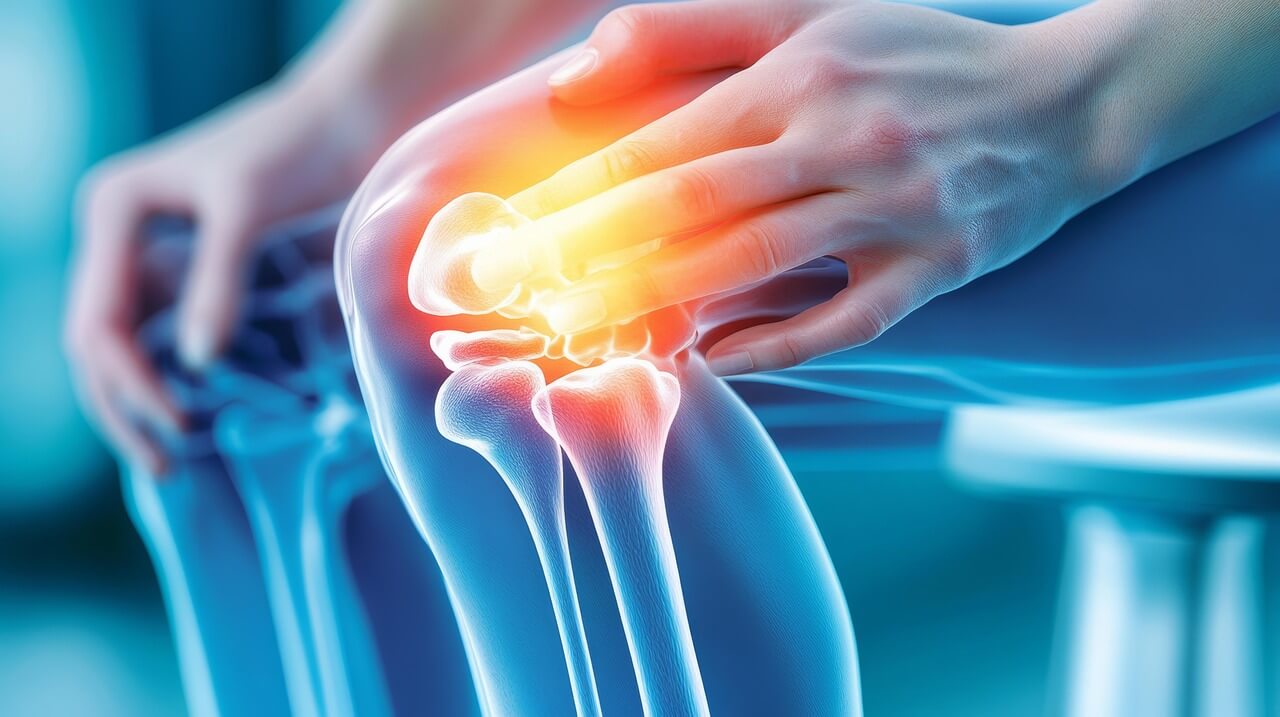

4-2. 영상 검사 (X-ray, MRI)

X-ray 검사에서는 관절 간격이 줄어든 것을 확인할 수 있으며, 진행된 경우 뼈의 변형도 나타납니다. MRI 검사는 연골 손상 정도를 더 세밀하게 파악할 수 있어 조기 진단에 도움이 됩니다. 이러한 검사는 관절염의 진행 정도를 정확히 알 수 있는 중요한 도구이므로 주기적인 검사를 권장합니다.